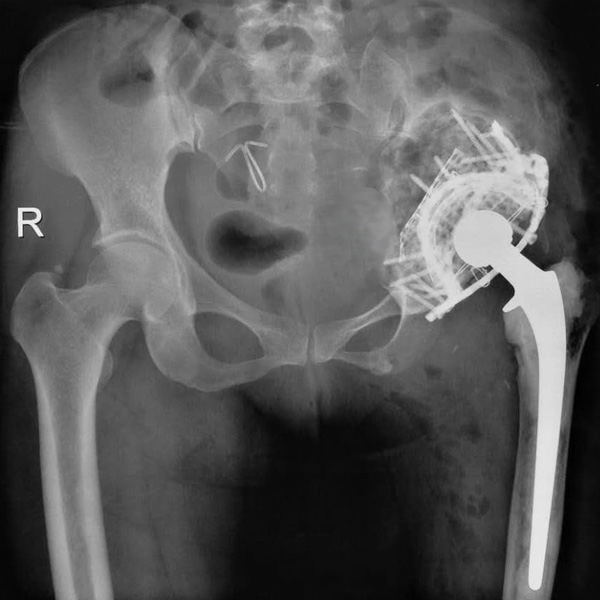

• 先天性髖關節脫位先天性髖關節脫位手術后手術前

先天性髖關節脫位

患者王某某,女,41歲,從會走路以來就發現一條腿長,一條腿短,也就是人們俗稱的“跛子”,之前雖然兩條腿長短不一,但起碼還可以走路,維......